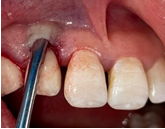

2 months after sealing (Figures 23–27). In implantology, connective tissue grafting is indicated at all stages of implant therapy to guarantee an optimal aesthetic result. Connective tissue tunnel grafts has been chosen. After 2 months of surgery, we note a good aesthetic result and the satisfaction of the patient.

Figure 23 Preparation of recipient site.